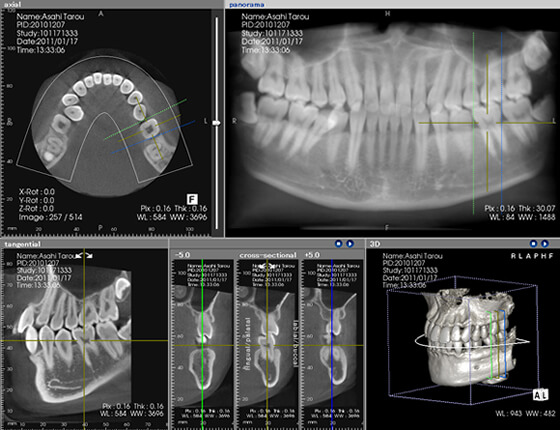

CTは顎の骨や周囲の組織の状態を撮影できる画像診断装置です。

歯周病になると、徐々に顎の骨が溶かされていってしまいます。

CT撮影をすることで歯周病の進行度合いを正確に知ることができ、適切な治療方法を選択できるようになります。